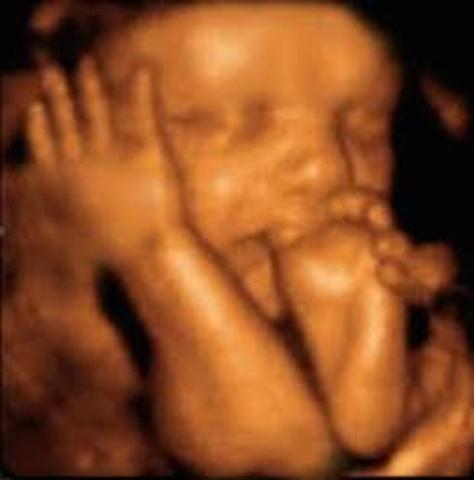

Semana 27 a 30

El cerebro del bebé crece rápidamente.

El sistema nervioso se desarrolla lo suficiente para controlar algunas funciones del cuerpo.

Los párpados del bebé se pueden abrir y cerrar.

El aparato respiratorio, aunque inmaduro, produce agente tensioactivo. Esta sustancia ayuda a que los alvéolos se llenen de aire.